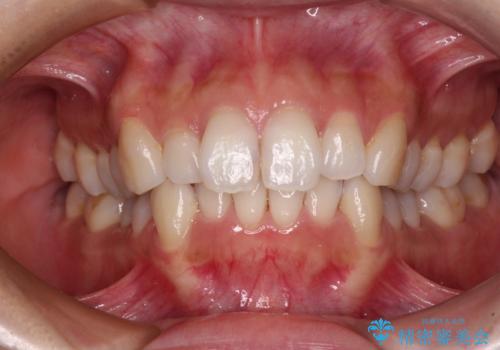

【非抜歯】インビザラインで正しい噛み合わせを

【非抜歯】インビザラインでガタつきと口元を改善!非抜歯でも印象が変わる矯正治療